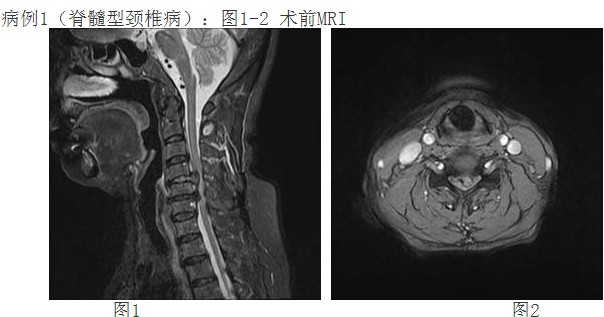

來自惠州農(nóng)村李阿婆有多年的頸椎病病史,一月前頸部癥狀加重出現(xiàn)頸痛及四肢麻木、刺痛,不能耐受,上肢手臂力量及握力下降。經(jīng)人介紹前來我院,經(jīng)惠州三院脊柱外科譚志宏主任仔細(xì)檢查,并結(jié)合頸椎MRI,明確診斷為頸4/5、頸5/6椎間盤突出癥并椎管狹窄,屬脊髓型頸椎病。同時(shí)認(rèn)為如果采取保守治療問題根本解決不了,只有手術(shù)治療才有康復(fù)的希望。頸椎手術(shù)在脊柱方面屬高難度、高風(fēng)險(xiǎn)手術(shù),在外科手術(shù)分級(jí)中屬于最高級(jí)別的Ⅳ級(jí)手術(shù)。

經(jīng)過譚主任和全科醫(yī)護(hù)人員充分的術(shù)前準(zhǔn)備和討論,對(duì)患者實(shí)施了頸椎前路頸4/5、頸5/6椎間盤摘除、頸5椎體次全切除、椎管減壓鈦網(wǎng)植骨融合、頸前路鈦板固定術(shù)。手術(shù)取得了成功。術(shù)后第二天,李阿婆的四肢麻木就明顯減輕,握手能力和手臂力量都明顯好轉(zhuǎn)。